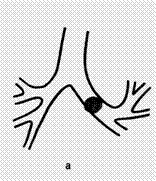

Так ознаками пухлини, яка не повністю закриває просвіт бронху, на бронхограммі

є дефект заповнення різної форми та довжини (в залежності від розмірів вузла та

його конфігурації). При повній обтурації бронху спостерігається симптом „культі"

чи „ампутації".